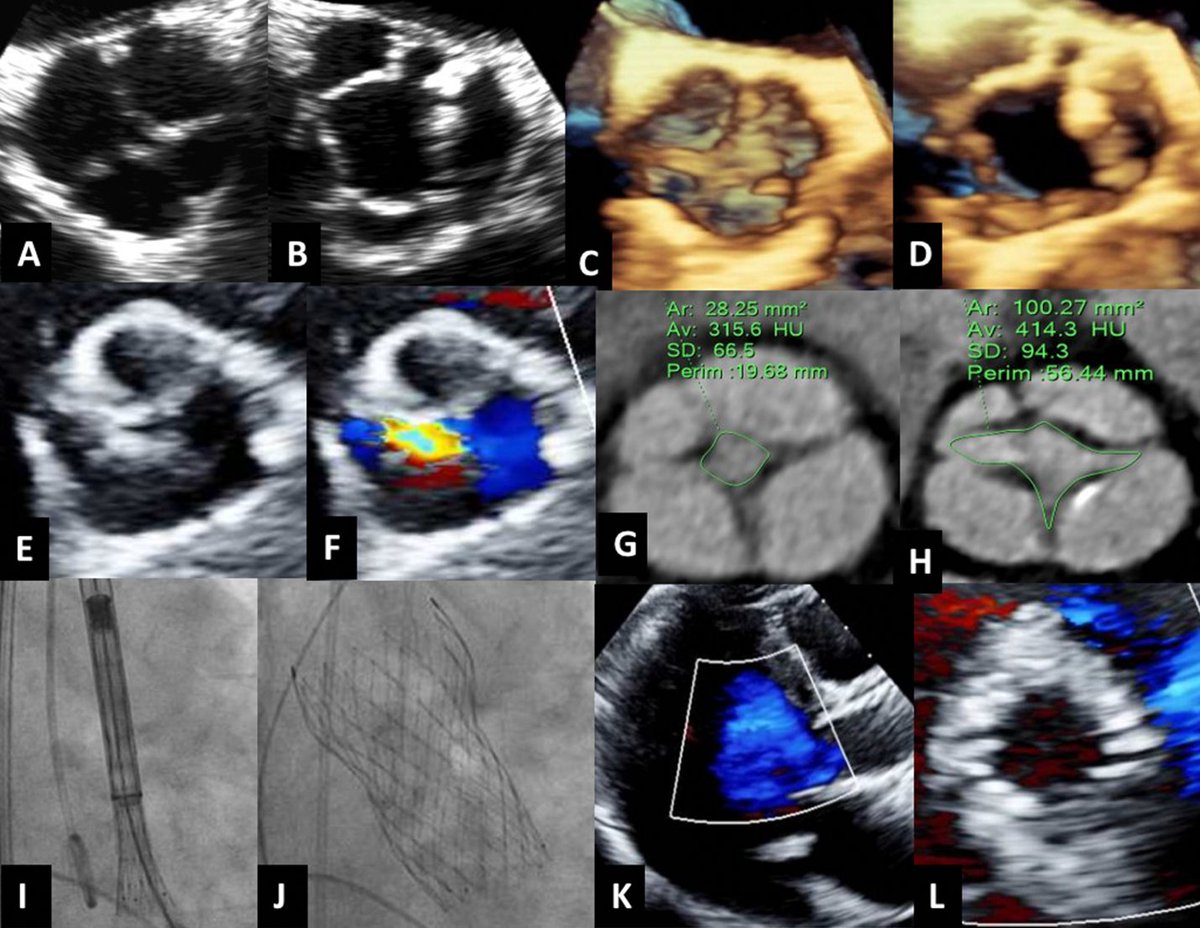

Official Account of the Advanced Cardiovascular Imaging Fellowship at The Mount Sinai Hospital.